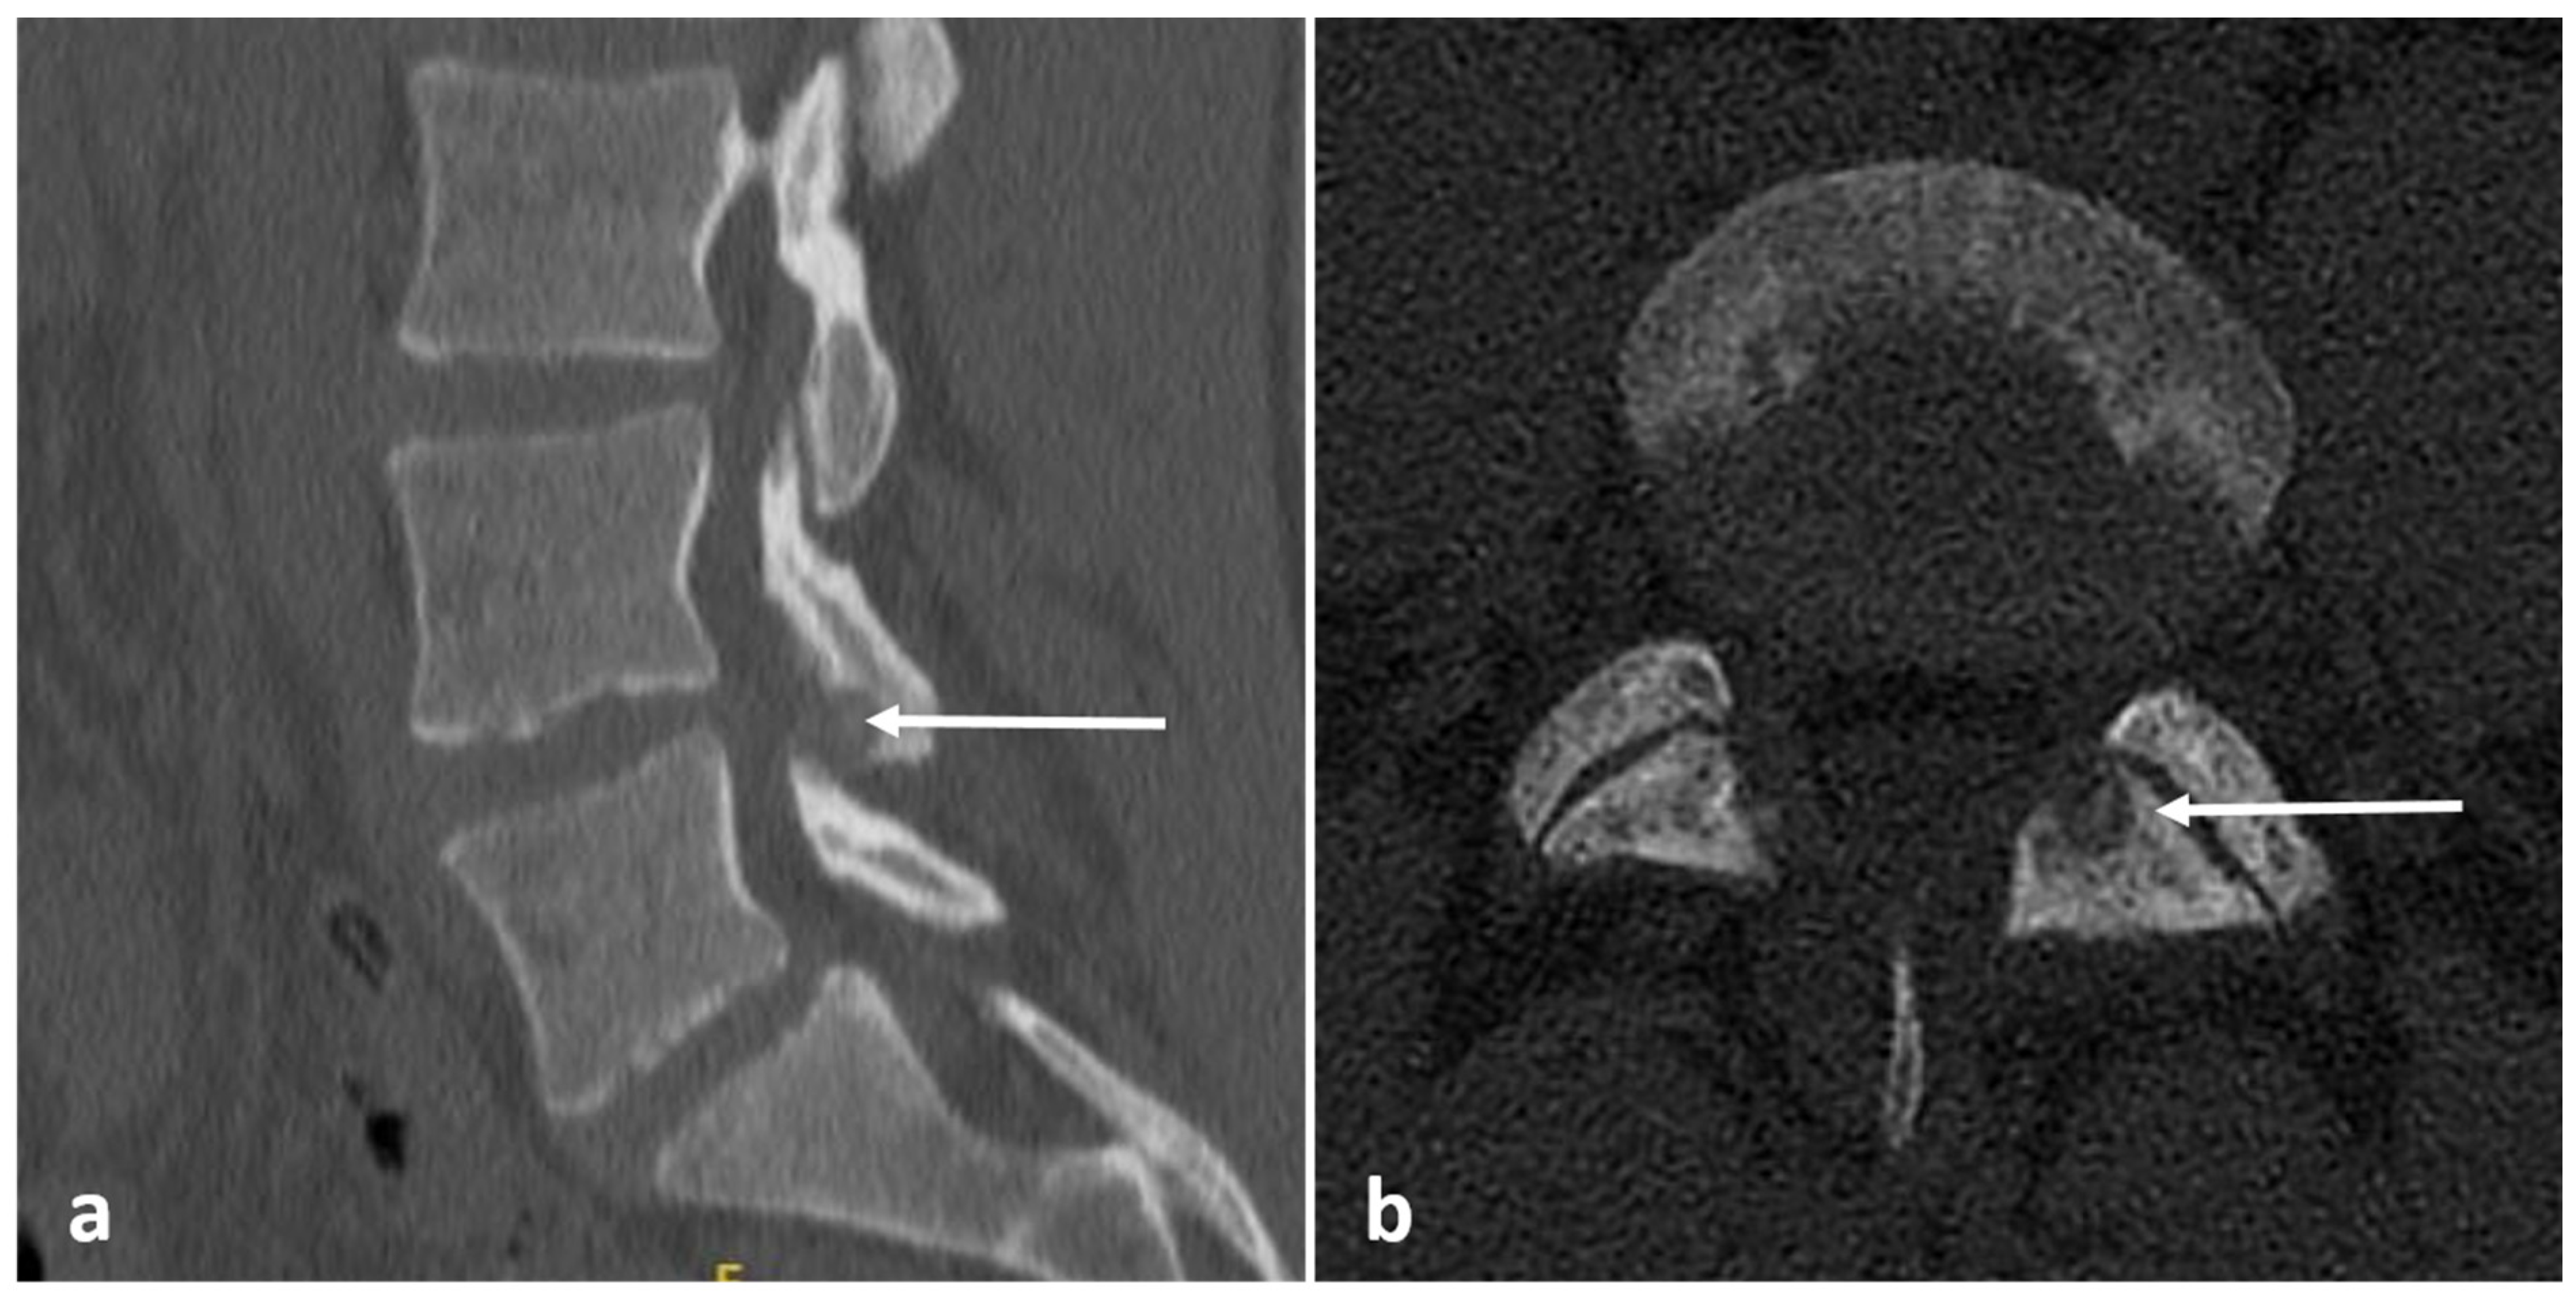

| Eosinophilic granuloma | Lucent lytic lesion, with bone destruction. Vertebra plana. | Non-specific appearance, with low T1 and high T2 signal. Diffuse enhancement. |